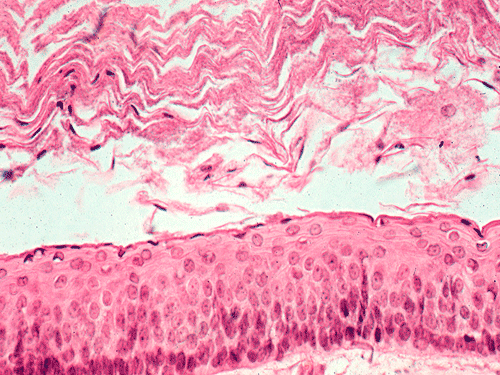

A tooth is present in the specimen. The soft tissue component consists of keratinizing squamous epithelium of rather even thickness of about 5-8 cells thick supported by a fibrous stroma without significant inflammatory cell infiltration (Panel B & C). Keratinaceous debris shredding from the surface of the epithelium is noted. Note that parakeratosis (retention of nuclei in the keratinized layer) is present  (Panel C). Good polarization is noted in the epithelium although there are some basal hyperplasia and palisading arrangement of the basal layers. The nuclear looks slightly immature and some with a small but distinct nucleoli. These are features of some low grade dysplasia.

This is a cystic neoplasm lined by keratinizing squamous epithelium without atypia, with keratinaceous debris in the lumen similar to that seen in epidermal inclusion cyst. A creamy cystic content may be seen during surgery. The palisading basal layer is a good hint for recognizing this entity. Orthokeratinized odontogenic cysts do not have this palisading arrangement and they have much lower recurrence rate. The parakeratosis also separate this entity from orthokeratinized odontogenic cysts. It can be unilocular to multilocular. It can be inflamed. Marsupialization of the cyst and flushing with caustic agent will change the morphology and lead to a nondescript stratified squamous epithelium with chronic inflammatory cell infiltration in the supporting stroma. Satellite cysts can be seen at the periphery of the tumor and may be related to recurrence therefore these features should be reported. This tumor can perforate bone.